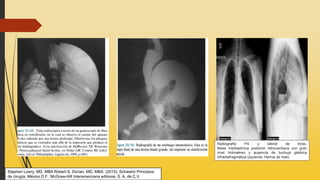

Figura 25-39. A. Radiografía de una hernia hiatal tipo I (por

deslizamiento). B. Radiografía de una hernia tipo II (por

rodamiento o paraesofágica). (Continúa)

Figura 25-39. (Continuación) C. Radiografía de una hernia tipo III (combinación

deslizamiento-rodamiento o mixta). D. Radiografía que muestra un estómago

intratorácico. Ésta es la fase terminal de una hernia hiatal grande, sin tomar en

cuenta su clasificación inicial. Obsérvese que el estómago ha girado 180 grados

alrededor de su eje longitudinal, con el cardias y el píloro como puntos fijos. (Con

autorización de DeMeester TR, Bonavina L: Paraesophageal hiatal hernia, en

Nyhus LM, Condon RE [eds]: Hernia, 3rd ed. Philadelphia: Lippincott, 1989, p

684.)

Radiografía PA y lateral de tórax.

Masa mediastínica posterior retrocardíaca con gran

nivel hidroaéreo y ausencia de burbuja gástrica

infradiafragmática izquierda. Hernia de hiato.